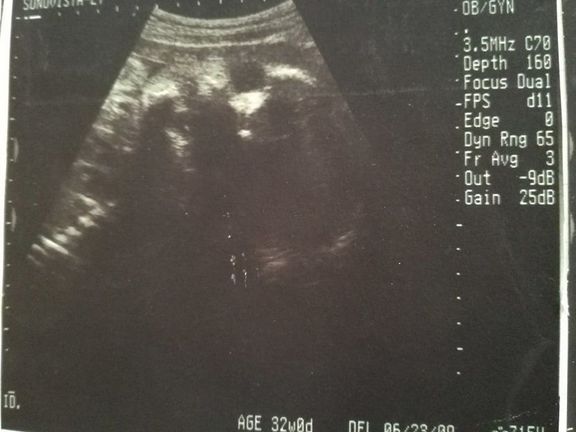

【応募すると全員もらえる】GELATO PIQUE エコー写真専用リフィルアルバム&エコー写真デジタルフレームが『初めてのたまごクラブ』冬号でもらえる!妊娠・出産

【応募すると全員もらえる】GELATO PIQUE エコー写真専用リフィルアルバム&エコー写真デジタルフレームが『初めてのたまごクラブ』冬号でもらえる!妊娠・出産 -

【応募すると全員もらえる】GELATO PIQUE エコー写真専用リフィルアルバム&エコー写真デジタルフレームが『初めてのたまごクラブ』秋号でもらえる!妊娠・出産

【応募すると全員もらえる】GELATO PIQUE エコー写真専用リフィルアルバム&エコー写真デジタルフレームが『初めてのたまごクラブ』秋号でもらえる!妊娠・出産 -